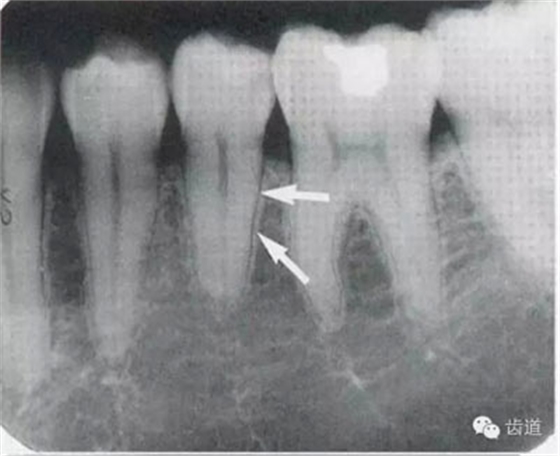

5)下頜管:

位于磨牙牙根尖下方,呈寬約為0.4cm凹面向下邊緣整齊的帶狀密度低的影像,其兩側(cè)有密度高的線條狀影像,為下頜管骨密質(zhì)